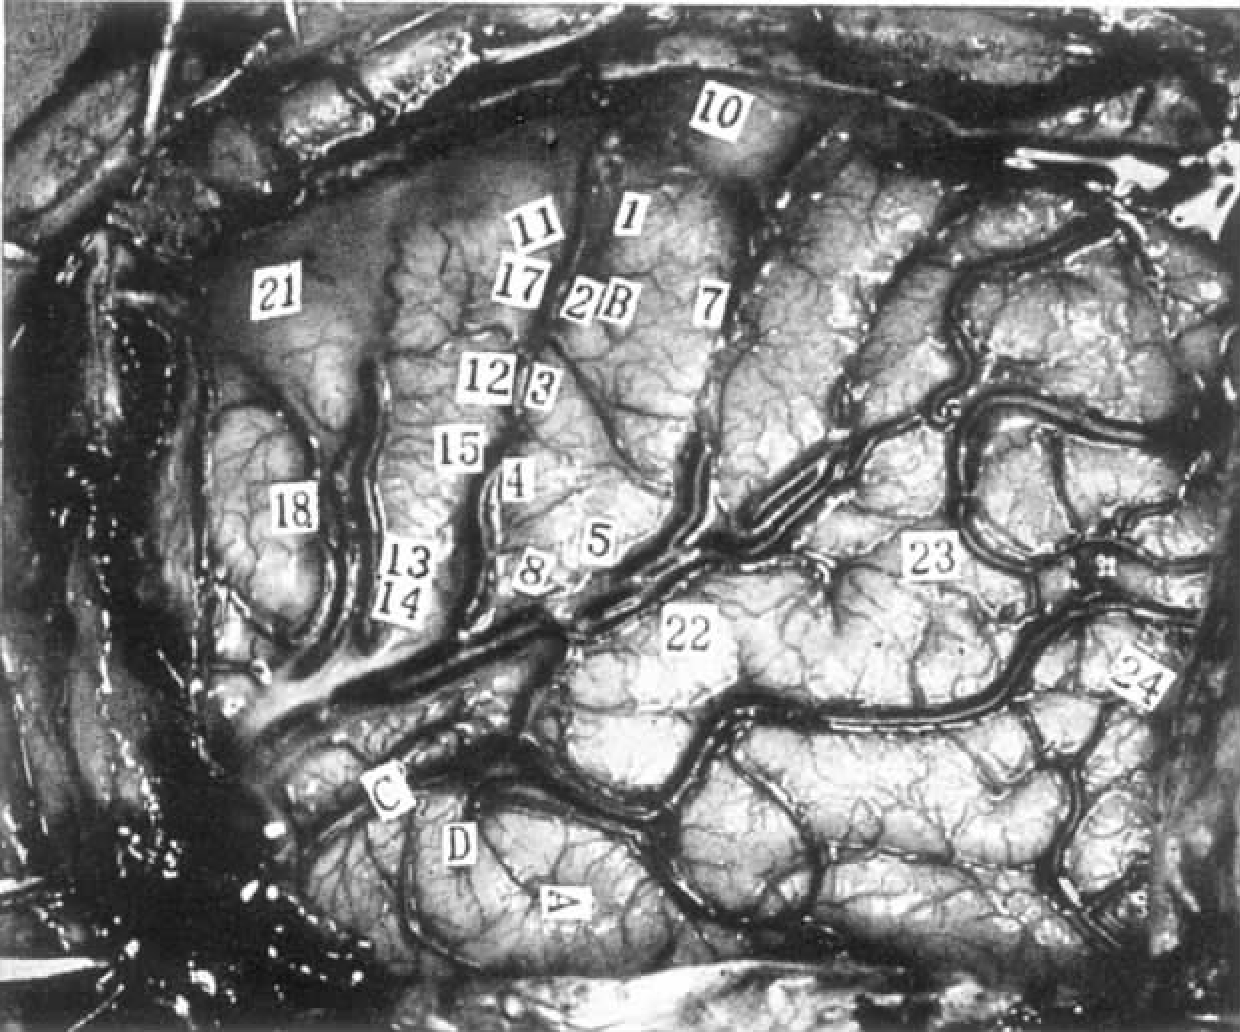

26岁,男性。出生时大脑受过伤,左侧中央沟后区是损伤最严重的部位(损伤范围见图4-1),他的外侧裂也向上移动了相当的距离。左利手。右侧面颊出现麻木感是癫痫发作的先兆。

左脑,近中央沟处的运动区,次级感觉区和次级运动区(见图4-1)。

图4-1 病例H.Fa.刺激点与所引起的反应

刺激条件:拉姆刺激仪,频率为60Hz,电压是1V,1.5V和2V。没有发作后放电。

20 “我手臂没有力气。”患者后来说,“我感觉好像失去了它,就像它不知不觉溜掉了一样。”让患者挤压麻醉师尼尔的双手。在无提醒的情况下进行刺激,这导致他右手挤压的力量突然减低,尽管他的左手仍继续施压。但在刺激结束时,右手挤压力突然又产生。

18 “右手出现奇怪的感觉,有移动的趋势。我相信它确实动了。”能观察到那只手手指轻微伸展。

18 重复刺激并要求患者保持手不动。这次手指没有运动。

18 要求患者双手互握。在随后的刺激过程中,他的右手几乎完全变松弛。但电极一撤除,他的右手又恢复握力。

20&18 皮层电位显示皮层活动抑制。其后各个电极依次产生慢波。

15 患者嘀咕着:“我双侧手脚都有感觉。这种感觉起始于脸部,可能主要是右脸。”当要求患者描述他的感觉时,他说:“那是种麻木的感觉,我的脚好像要抬起来。”

35 “我的右脚有轻微的感觉,似乎要将脚弓抬起来了。”

35 在病人的右脚做随意运动时重复刺激,运动没有被打断。很显然,他这次没有任何感觉。

33 肩膀和双手有感觉,主要是右侧。

12 脸部有感觉,他描述为围绕着嘴唇,在右侧。

12 一段时间间隔后,在无提醒的情况下重复刺激。他的右侧脸有感觉,可能也包括左脸,并向下延伸到躯体。

12 无提醒的情况下重复刺激,同时让患者用双手互握。刺激过程中,右手的力量明显下降。在刺激结束后,尼尔博士一声惊叫,因为他感到患者右手突然发力。

14 左脸有感觉,同侧身体也有轻微的感觉。

●该病例有脑回变形和移位的现象,这在产伤患儿的头部发育过程中经常发生。

●被称为次级感觉区的区域似乎位于中央前回向下延伸处,而产生感觉的部位包括身体两侧,对侧稍强。感觉包括麻木感和该部位好像要朝特定方向的移动。

●刺激点20的运动效果与刺激次级感觉区的效果相似。有一种要失去它的感觉,而且毫无疑问,对侧手臂随意动作麻痹与电位抑制相关。这种抑制作用在刺激撤除后便立即消失。对相邻的点12的刺激造成随意动作的力度降低,但不会麻痹。

●本病例有两个现象与随意运动系统有关:一是运动感觉或是一个部位即将要运动的感觉,二是对随意运动的抑制。

本例主要是对患者左脑,近中央沟处的运动区,次级感觉区和次级运动区进行刺激。引起的反应主要包括:对对侧肢体随意运动的抑制,麻木感和该部位好像要朝特定方向移动的感觉。